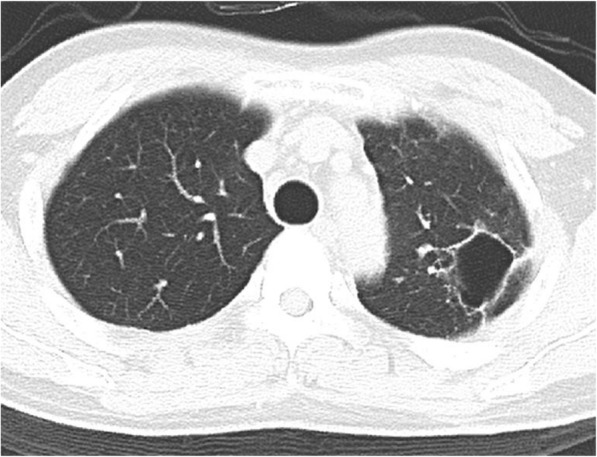

Fig. 1.

Computed tomography findings before and after initial percutaneous drainage. a A large abscess with an air-fluid level in the left upper lobe. b Residual abscess content due to incomplete initial drainage